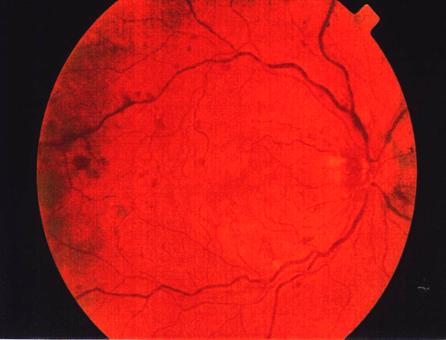

Fig. 1

Obstructie de vena centrala a retinei